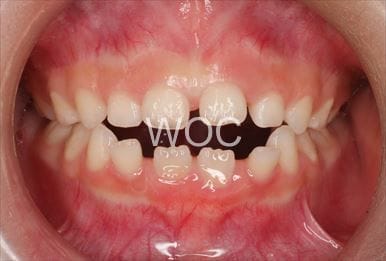

叢生

治療前1

治療前2

治療前3

治療前4

治療前5

- 年齢:7歳9ヶ月

- 主訴:スペースがない、デコボコしている

- 診断名:叢生、上顎前突、過蓋咬合

- 装置:可撤式拡大装置、機能的矯正装置

- 期間:4年1ヶ月 ※

- 費用:基本矯正料金:380,000円